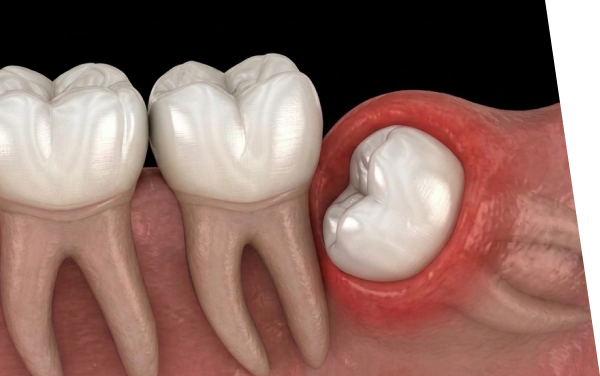

- 斜めや横向きに生えている

- 歯ぐきの腫れや痛みを繰り返している

- Q2 親知らず抜歯後は腫れますか?

-

A2

はい。腫れは抜歯後2〜3日をピークに、多くの場合は数日〜1週間ほどで落ち着きます。

特に埋まっている親知らずは腫れやすい傾向があります。保冷剤をタオルで包んで軽く冷やすのがおすすめです。腫れが強い場合はご相談ください。